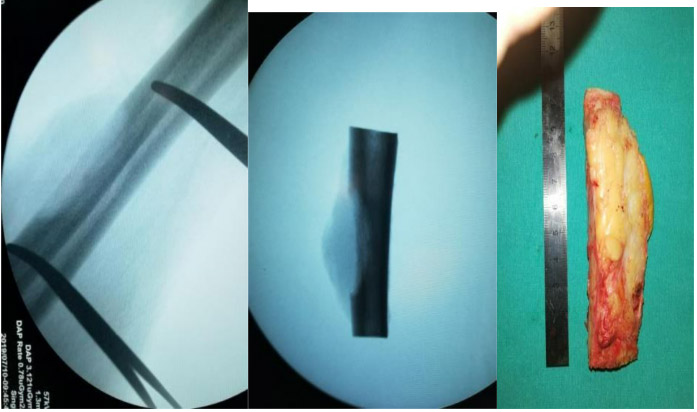

During the operation: Removal of the tumorous part of the bone